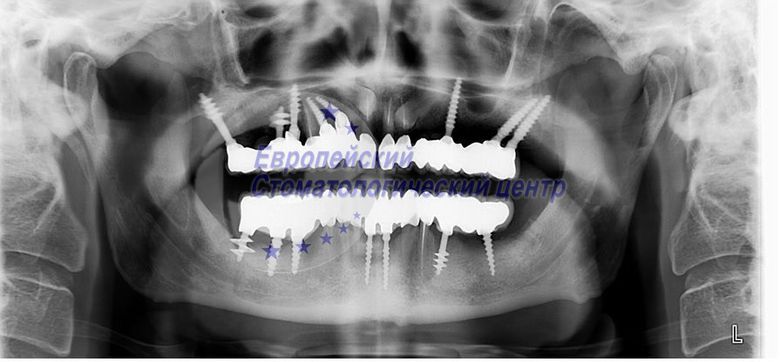

ОЗУ через 5 років після операції